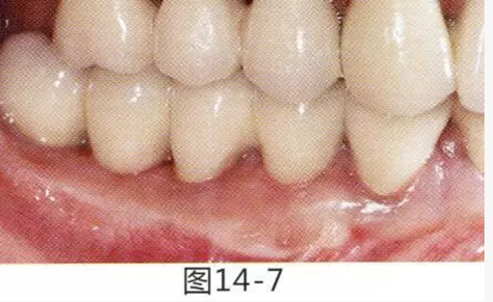

圖14-1 修復體周圍角化牙齦較少,很難進行清潔的狀態(tài),并有緣下齲壞的發(fā)生。

圖14-7 配戴最終修復體完成5年后的狀態(tài)。保持良好。